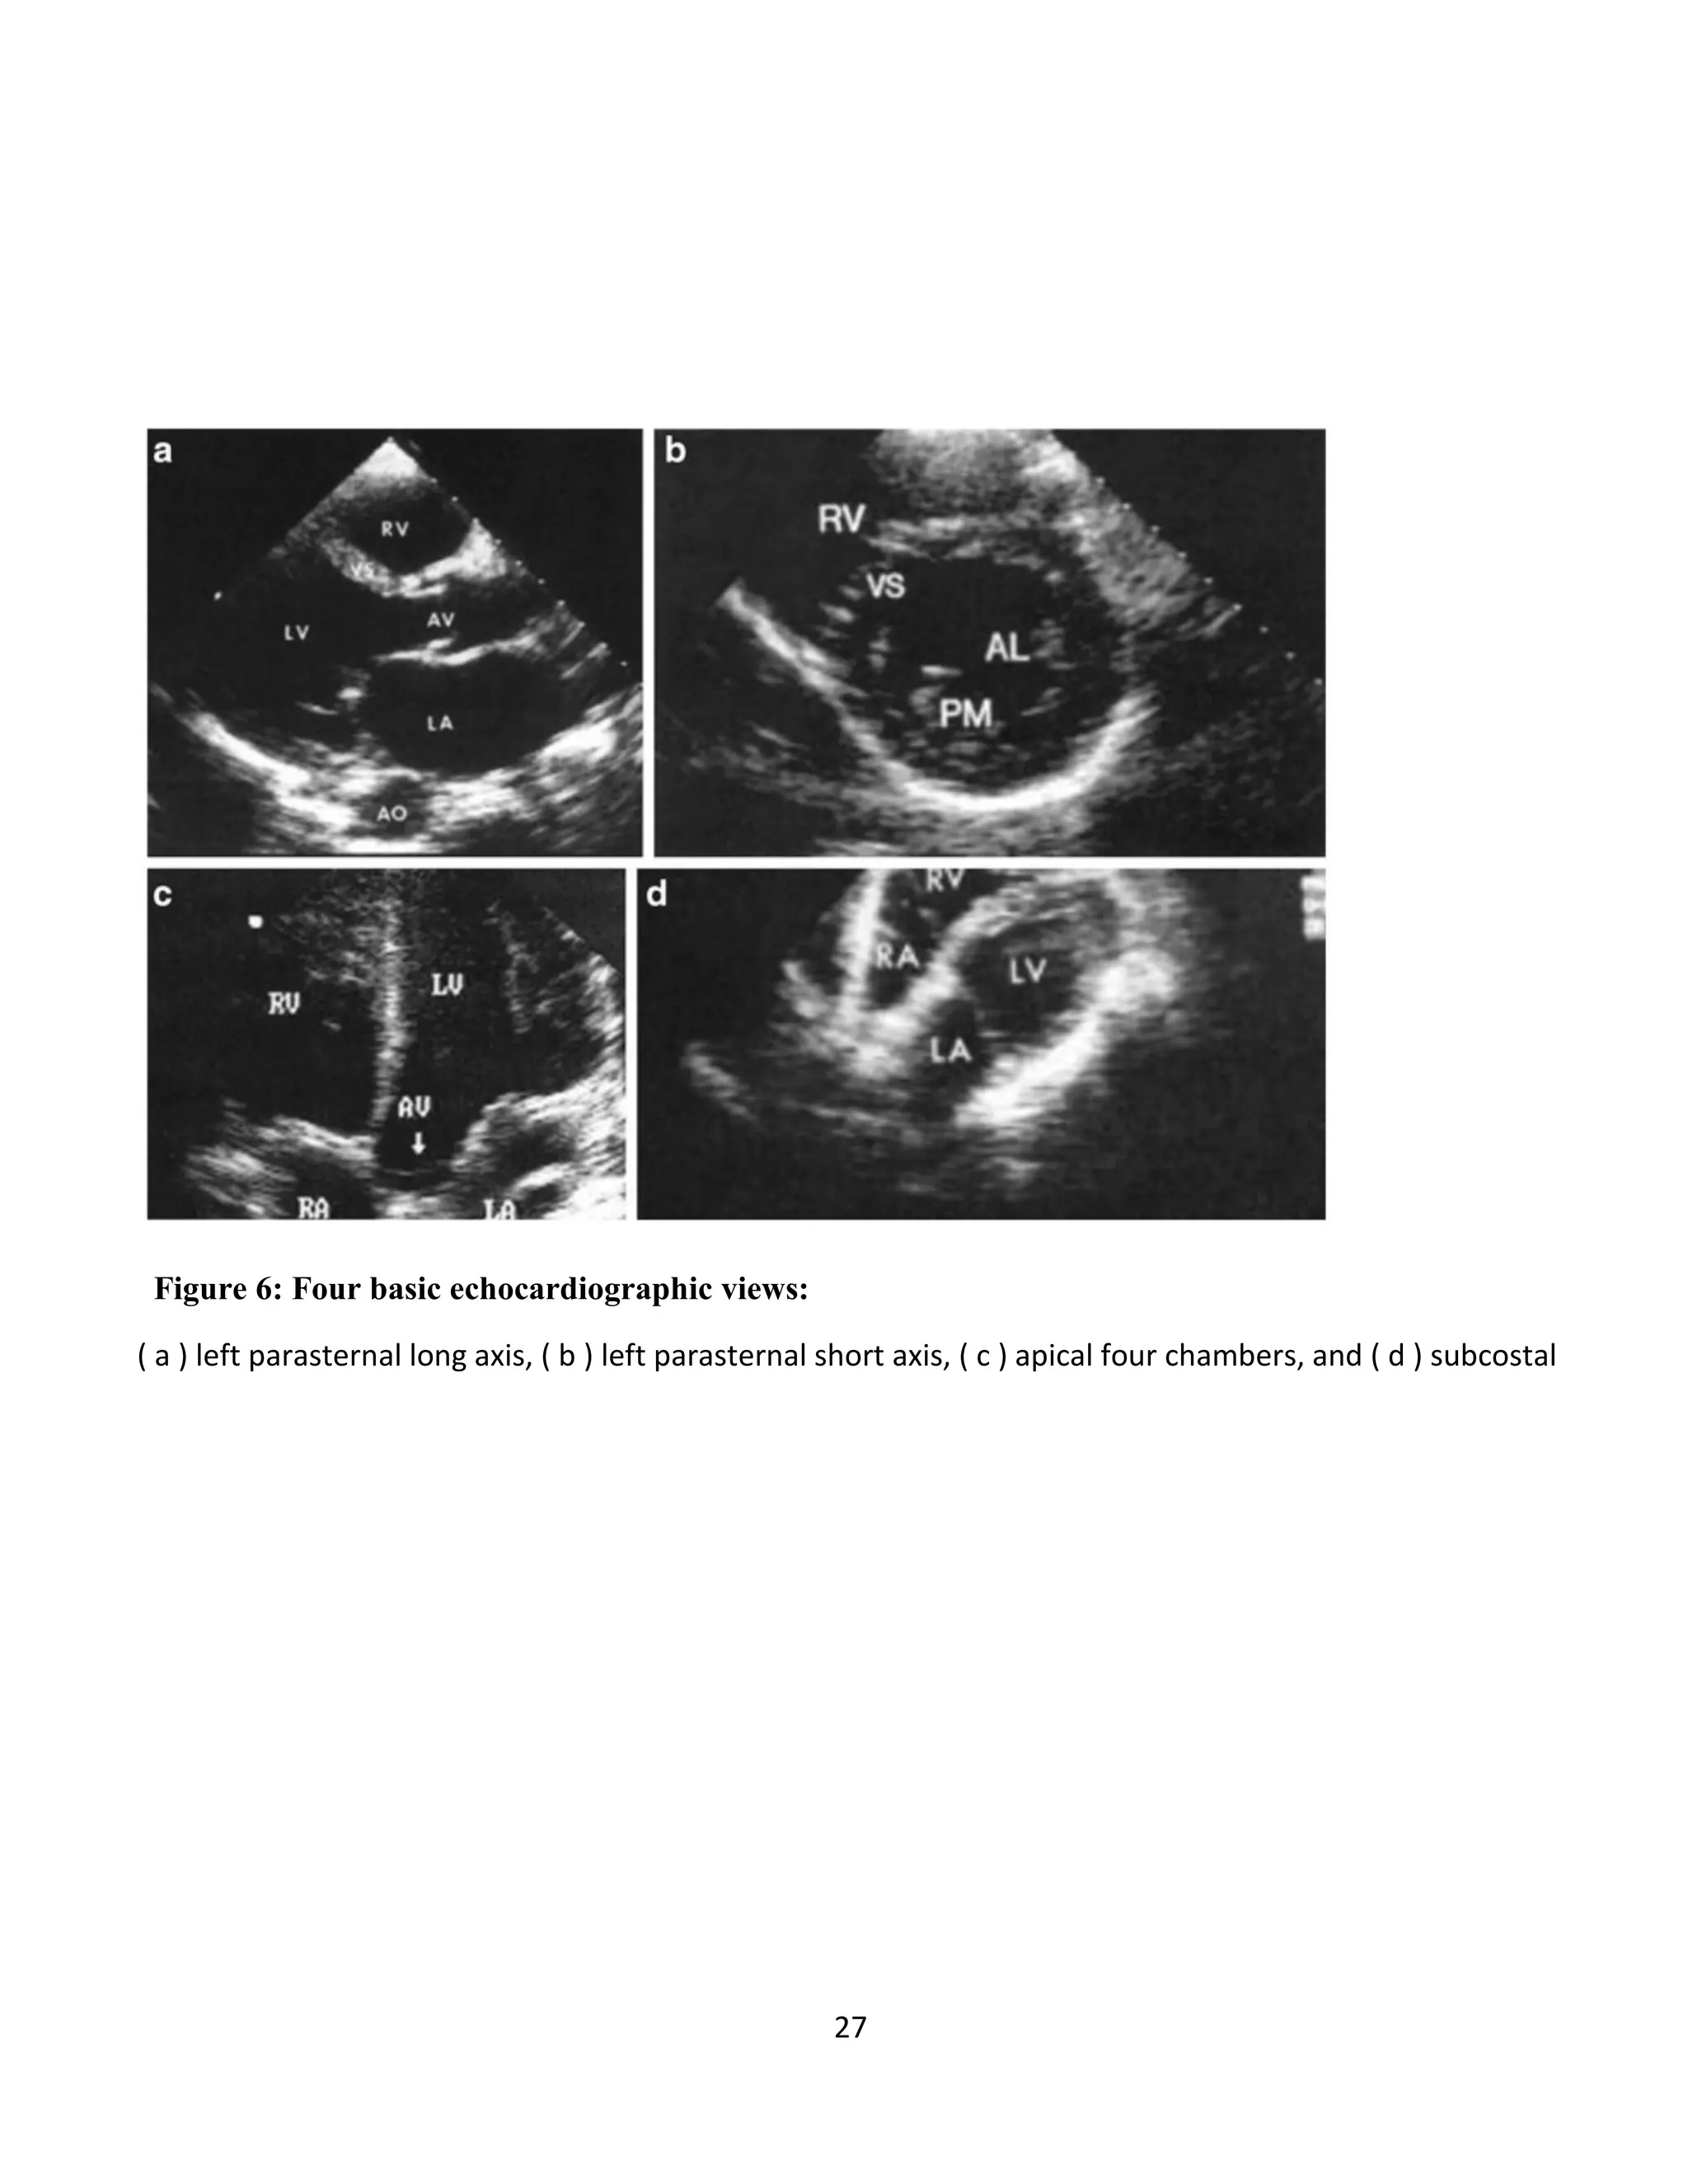

Figure 6: Four basic echocardiographic views:

( a ) left parasternal long axis, ( b ) left parasternal short axis, ( c ) apical four chambers, and ( d ) subcostal

3. What is the status of cardiac function? (Figure 3)

b. Evaluation of Left Ventricular Contractility

i. The left ventricle can be analyzed for global contractility in left parasternal long axis

and short axis view

ii. Based on these assessments, a patient’s contractility can be broadly categorized as

being normal, mild-moderately decreased, or severely decreased.

c. Evaluation of Right Ventricular Size

i. Evaluation of right ventricular size in left parasternal long axis view, apical 4

chamber view, and/or subxiphoid view

ii. Signs of higher pressures within the right side of the heart and the pulmonary

artery include:

1. Dilation of the right ventricle, especially to a size equal to or greater than

the left ventricle

2. Deflection of the inter-ventricular septum toward the left ventricle